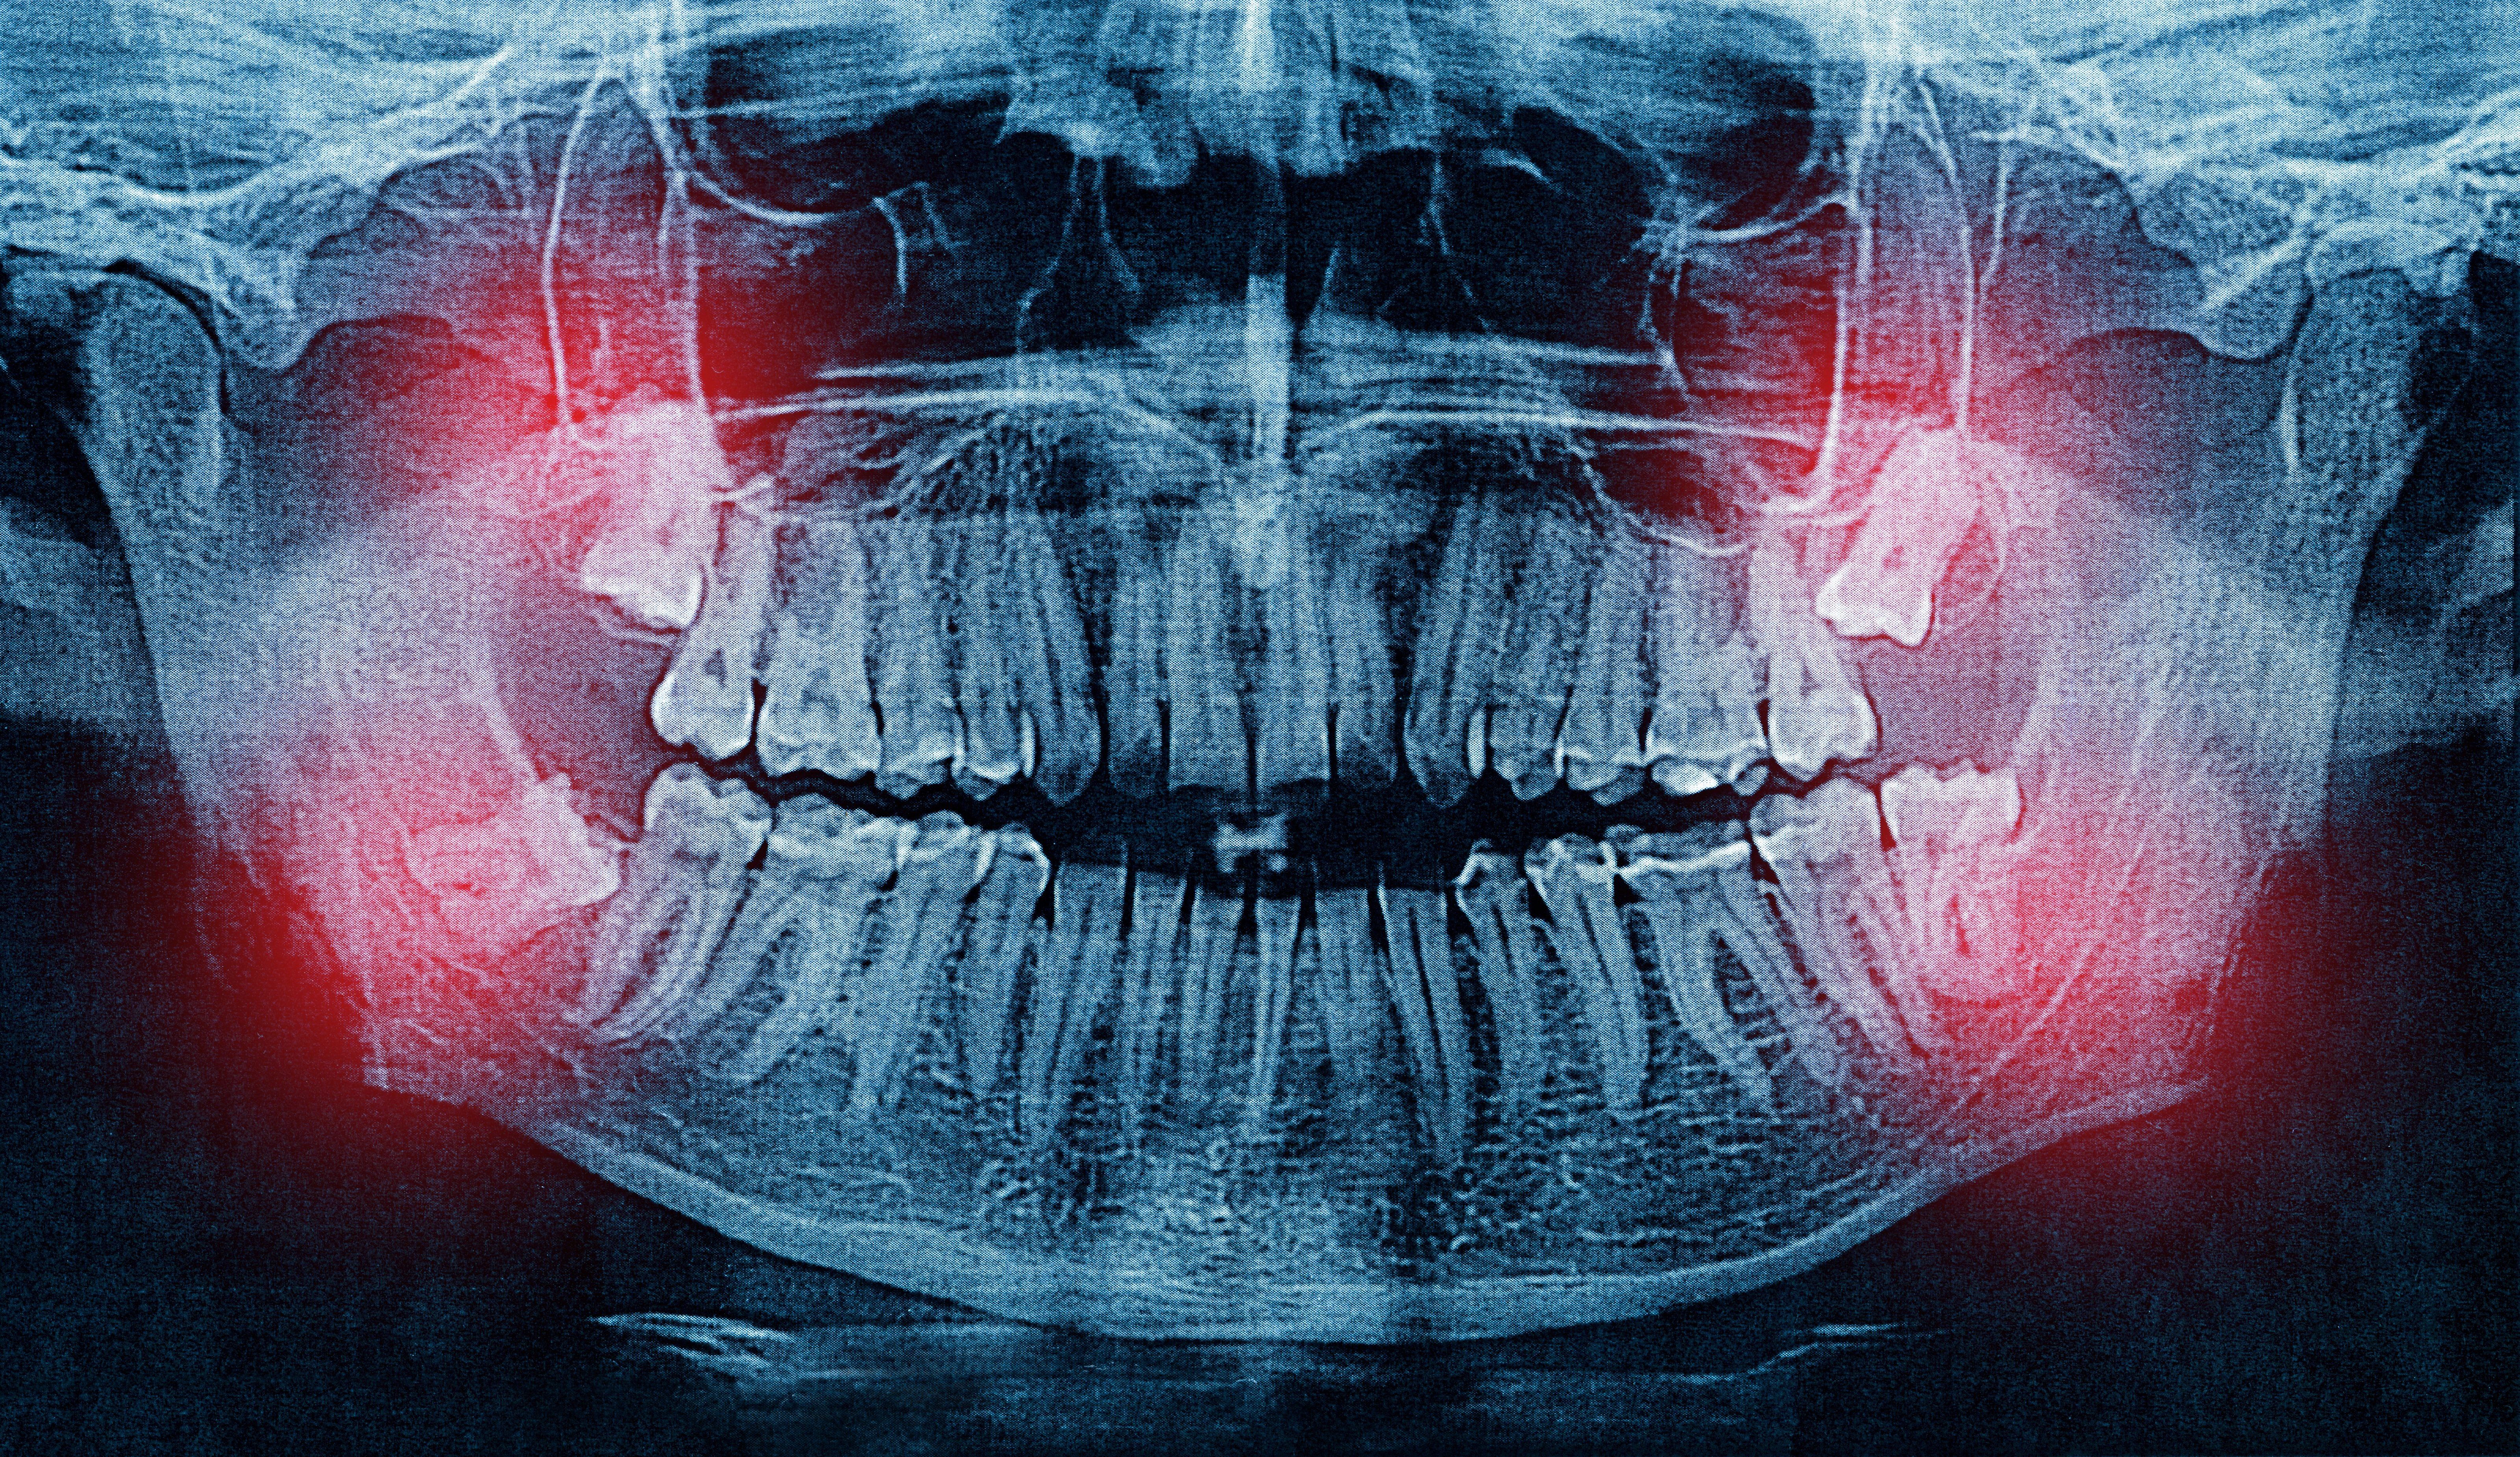

Wisdom teeth, also known as third molars, are the last teeth to develop and often do not have enough room to emerge properly. When they become impacted, partially erupted, or grow at an angle, they can cause pain, crowding, infection, and damage to neighboring teeth. Removing them proactively can prevent these complications before they cause lasting harm to your oral health.

At Jennifer Lopez Dental in Miami, Dr. Lopez uses CBCT cone beam imaging to see the exact position of your wisdom teeth relative to nerves, sinuses, and adjacent roots. This detailed 3D view allows her to plan the removal with greater safety, accuracy, and efficiency than traditional X-rays alone. The procedure is performed under local anesthesia, and most patients return to their normal routine within three to five days.

3D imaging maps the exact position of each wisdom tooth relative to nerves, allowing Dr. Lopez to plan removal with precision.

Dr. Lopez evaluates your wisdom teeth with 3D CBCT scans to assess their position, root development, and proximity to nerves — ensuring the safest approach for removal.